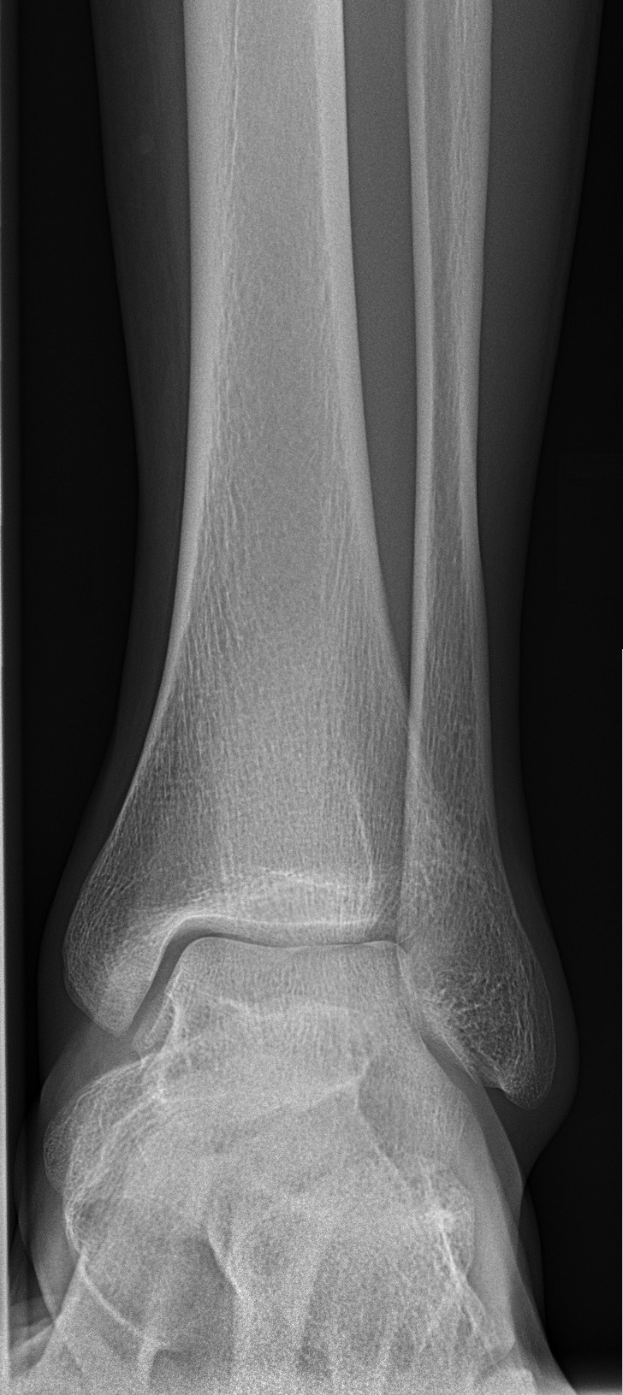

Schalkes 20-jähriges Nachwuchstalent Mika Khadr hat sich eine schwere Knöchelverletzung zugezogen, die ihn monatelang außer Gefecht setzen wird. Der Mittelfeldspieler brach sich am Sonntag, dem 14. März 2026, während eines Spiels in der Regionalliga West den Knöchel. Eine Operation hat bereits bestätigt, dass er für den Rest der Saison ausfällt.